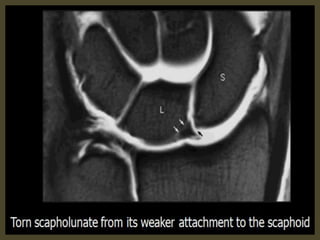

Scapholunate ligament rupture.

Scapho - lunate ligament tear